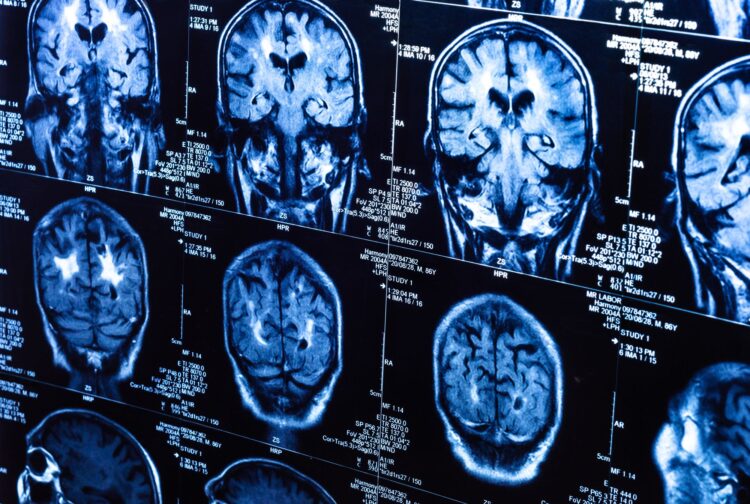

MRI

Magnetic resonance imaging does the same exact thing as computed tomography but uses magnetic fields to obtain the images.

MRI is especially precise and accurate when trying to uncover cancerous or tumor cells to a specific part of the body. This includes the liver and the nervous system (the brain). This technique is especially common in today’s medicine and is all possible through the discovery of the magnetic field in science.

With that said, MRI uses a magnetic field onto a laying patient while they’re inside a huge device called a scanner. The machine does use some radiation to help obtain the images. MRI uses the radiation with the magnetic field to align the hydrogen atoms in our tissues. Once everything is done, the atoms are aligned back into their original state and the machine gives us a 3D image of our body. Again, same as computed tomography, we can inject dyes for obtaining a clearer image.